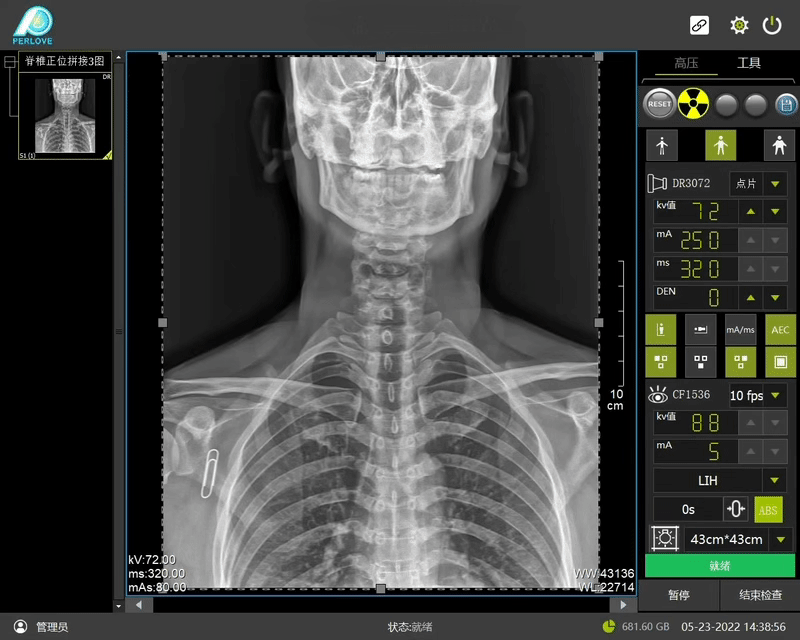

▲普利德多功能動態(tài)DR

動態(tài)DR全景拼接功能突破平板尺寸長度限制,可進行立臥位攝影,對脊柱、下肢及下肢靜脈造影進行分段攝片,然后對分段圖像進行拼接,在一幅X光圖像上完整顯示全脊柱或下肢整體形態(tài),獲得全脊柱或全下肢圖像,有效解決了傳統(tǒng)X光片不能一次成像問題,通過直觀顯示脊柱和下肢的整體解剖形態(tài)及側(cè)凸部位,為臨床治療提供重要參考依據(jù)。

普利德多功能動態(tài)DR進行全脊柱全下肢圖像拼接時,影像密度均勻、清晰、接緣處過渡自然,圖像質(zhì)量高,完全能滿足臨床觀察、診斷及測量要求。拍片過程也更加方便快捷,使患者得到快速診斷,及時治療,為臨床醫(yī)生和患者帶來更大的便利,大大助力醫(yī)院醫(yī)療服務(wù)能力的提升!